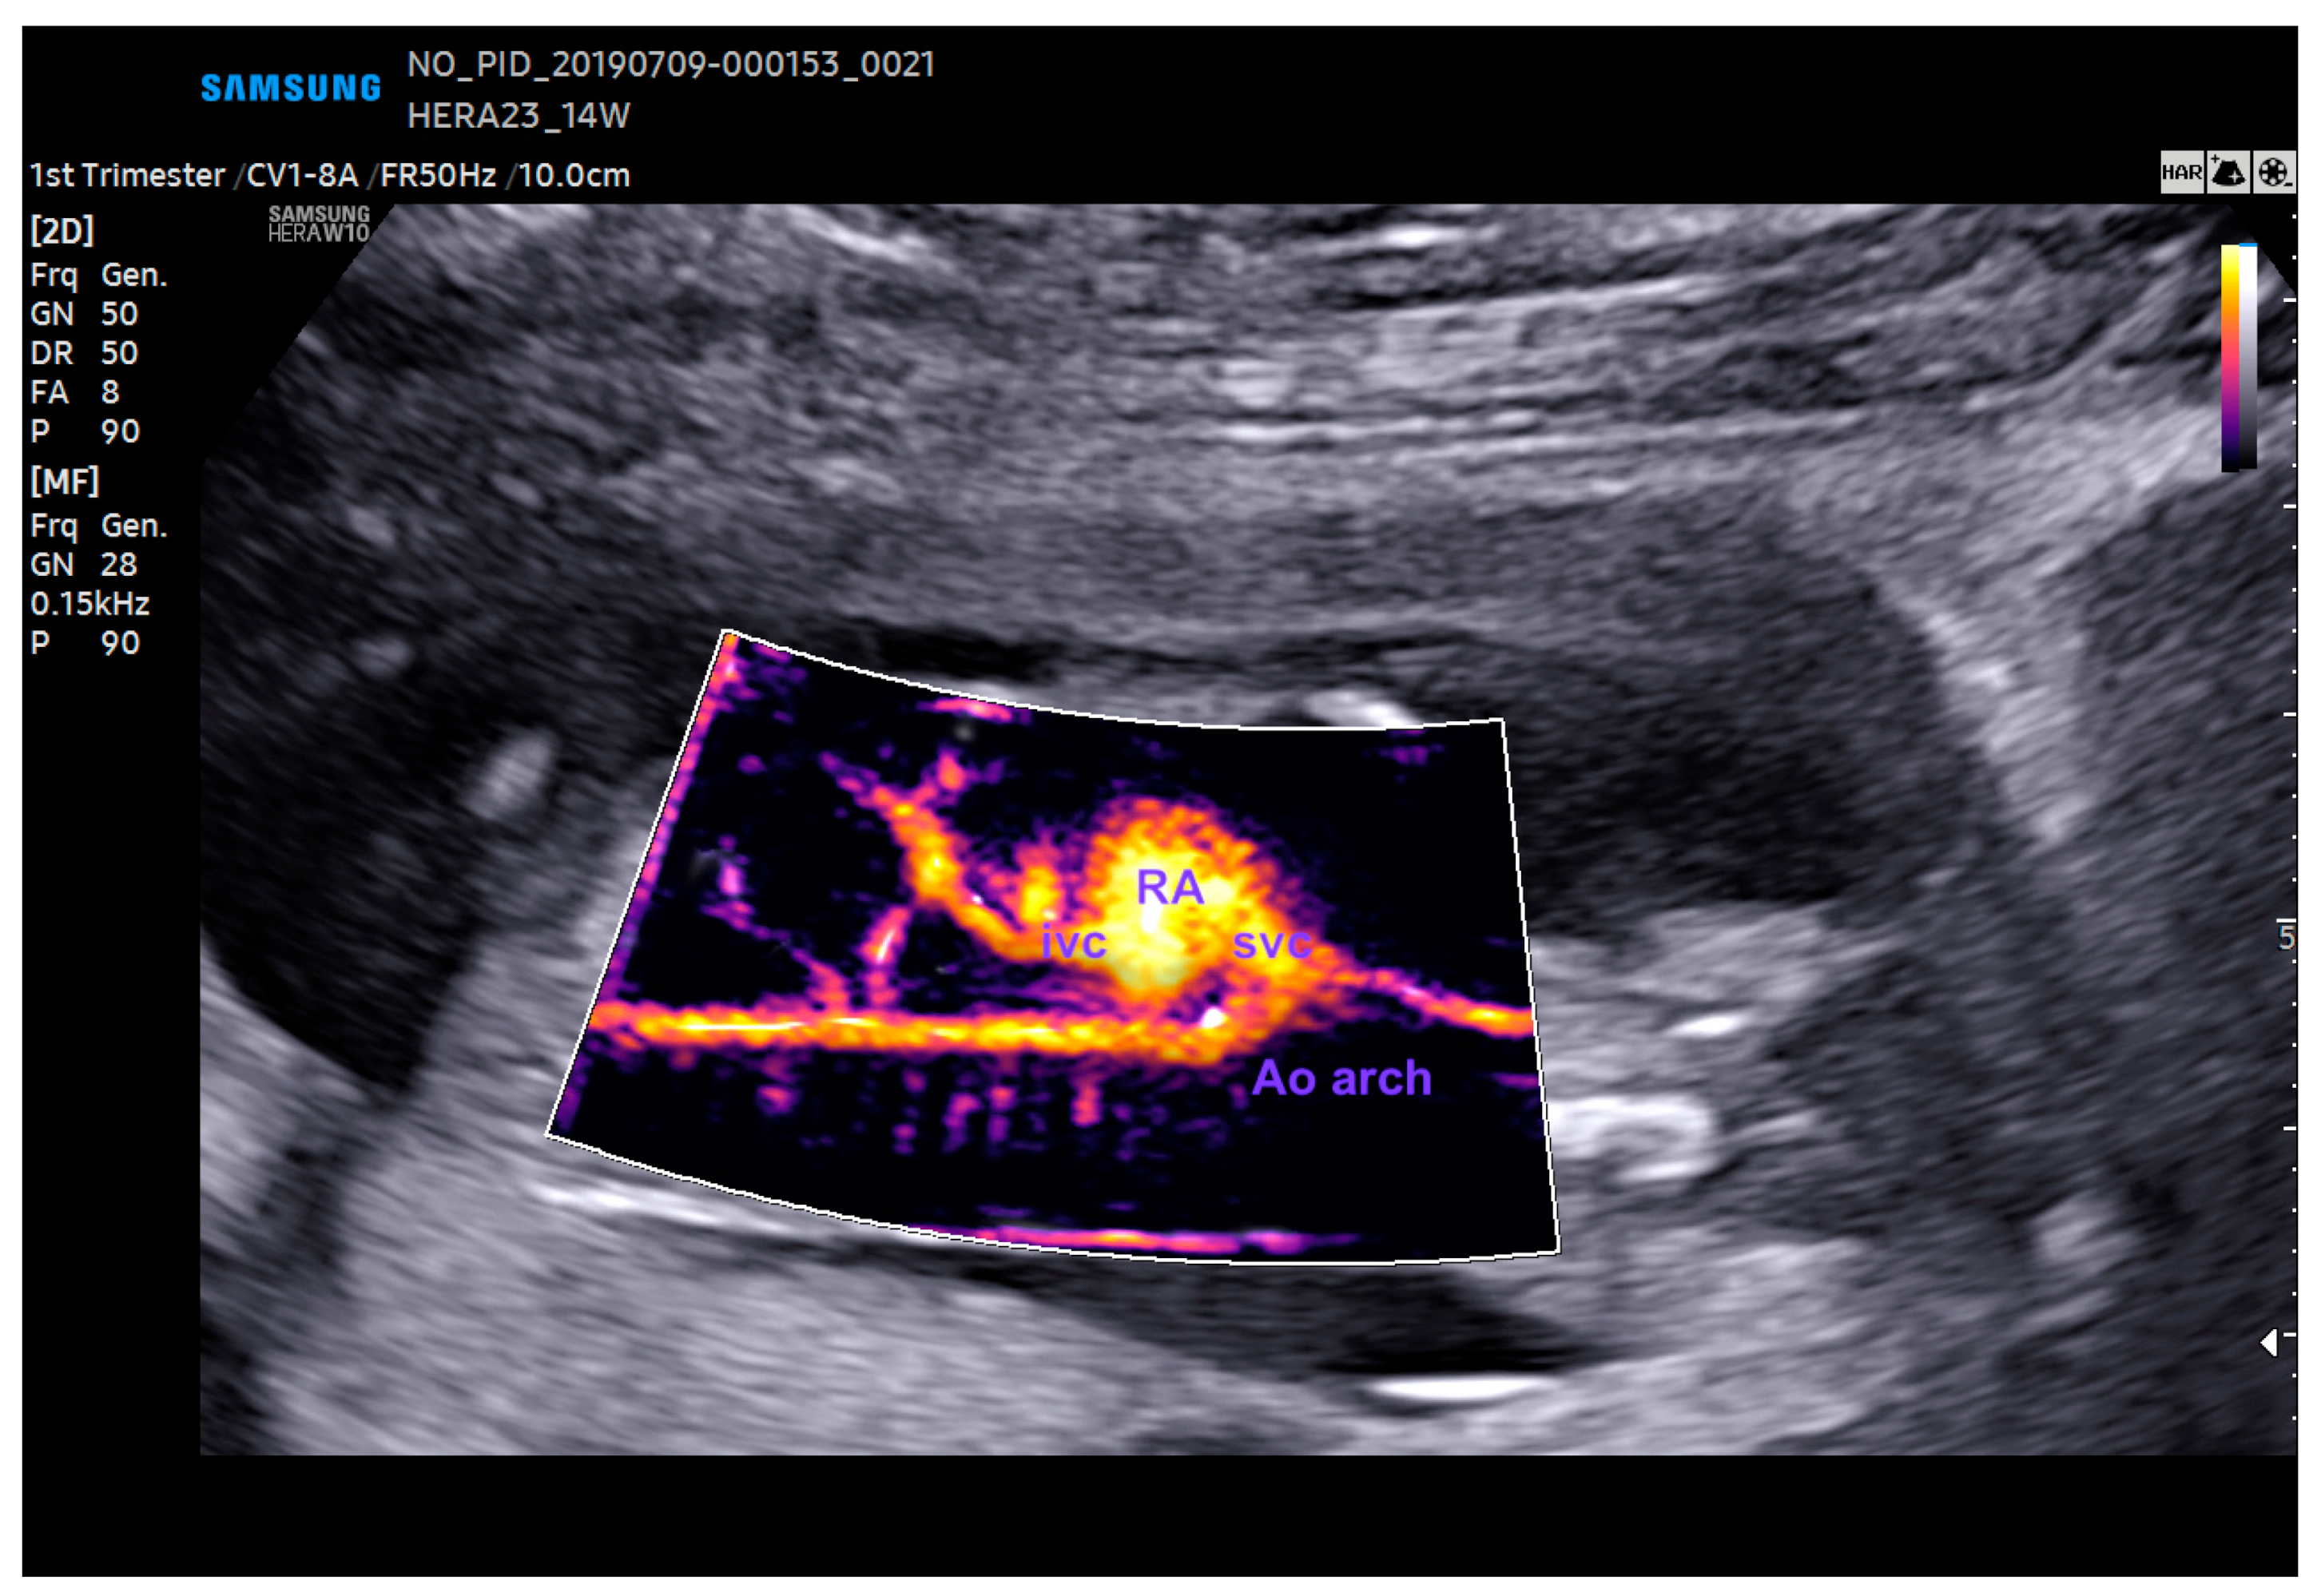

11. Anomalous Venous Return

12. Right Aortic Arch